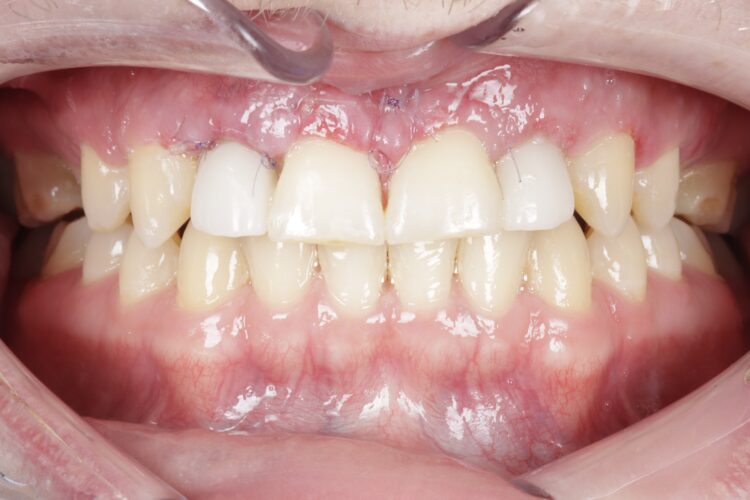

After completing orthodontic treatment, the patient attended a workup appointment, which included a CT scan, intraoral scans and pre-surgical photos and measurements.

The implant surgery was performed in May 2023 and was filmed live as part of a surgical demonstration for the delegates on a guided surgery course being run by the Fitz Fahey Academy. Implants were placed in the UR2 and UL2 spaces with simultaneous hard and soft tissue grafting. Following the surgery, the patient was provided temporary teeth and instructed to avoid putting undue pressure on the implants during healing.